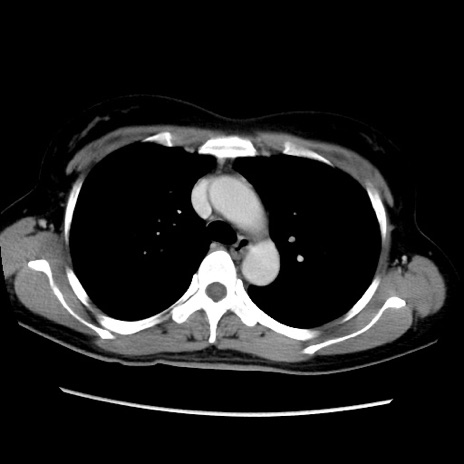

MRI(4日後)

【症例】40歳代女性

【主訴】上下腹部痛

【現病歴】2日目から下腹部痛あり。夜間は痛みで眠れなかった。昨日より上腹部痛と下痢が出現。臥位で痛みは軽快したため、休んでいた。本日になって臥位でも立位でも痛みが強くなってきたため救急要請。

【既往歴】子宮内膜症

【身体所見】部:平坦・軟、左上下腹部に圧痛あり、反跳痛あり。

【データ】WBC 21800、CRP 26.78